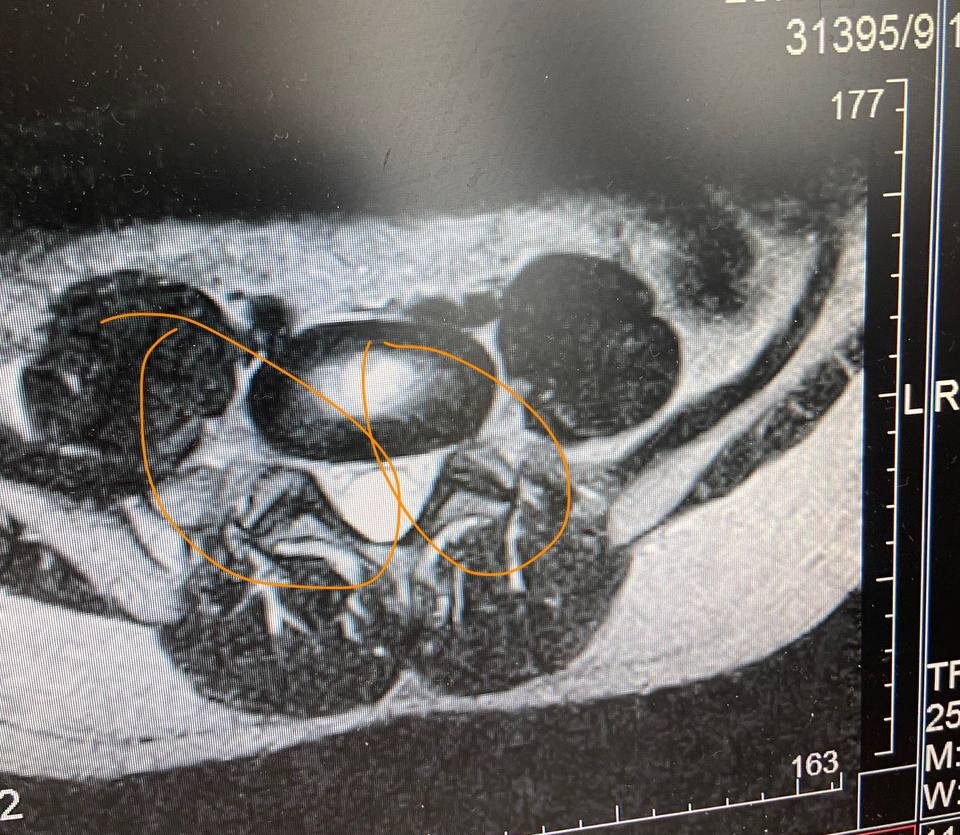

Этот перекос нужно как то выровнять

Попробуем выгрузить снимок с диска и для начала кому-то послать .